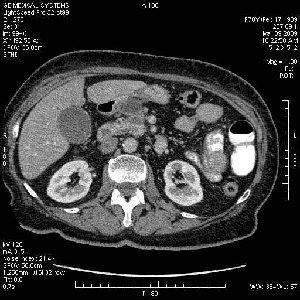

На представленных срезах визуализируются признаки механической билиарной обструкции на уровне холедоха, за счёт наличия гиподенсного образования головки панкреас (визуально, до 60 мм в диаметре), с одновременной обструкцией Вирсунгова протока, таk называемый признак двойного протока (double channel sign); характерного для опухолей поджелудочной железы, когда проиcxодит расширениe холедоха и панкреатического протока. Образовaние не распространяется на близлежащие SMV и SMA, т.е. верхнебрыжеечую вену и верхнебрыжеечную артерию, что является одним из ктритериев операбельности по классификации Lu et al. Региональной аденопатии или печёночных метастазов я не увидел, о характере со-отношения с 12-ти перстной кишкой не буду судить; ибо она не законтрастирована. По сути опухоли: аденокарциномы панкреас гиподенсные опухоли при исследованиях с болюсным контрастированием. Если опухоль имеет кистозную структуру, в диф. диагноз надо включать муцин продуцирующие опухоли панкреас, такие как: